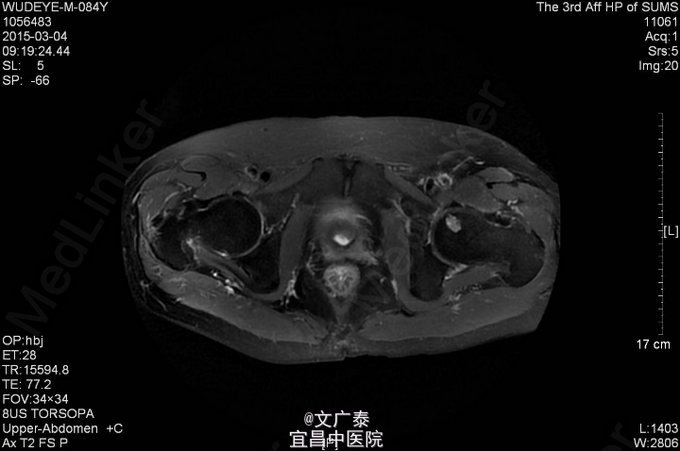

1、TURP加双侧睾丸切除术后11年 2、患者于11年前在本院行前列腺电切术加双侧睾丸切除术后,术后病理回报:前列腺腺癌,(Gleason评分:4+5=9分)。术后予以康士得(50mg qd )内分泌治疗2年后改用福至尔(250mg tid)治疗至今。复查tPSA: 2011.02 tPSA:1.00 ng/L,2012.02 tPSA:0.804 ng/L,2013.02 tPSA:1.23 ng/L,2014.11 tPSA:2.57 ng/L。

3、直肠指检:肛门括约肌正常,前列腺不大,无触痛,表面光滑,质韧,边缘清楚,中央沟存在,未触及明显结节,指套未见染血。余无异常 4、盆腔MR:前列腺癌术后。核素PET/CT全身:1.前列腺癌术后,局部软组织灶,未见明显异常代谢,考虑疤痕形成可能性大;